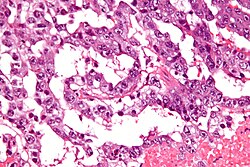

| Yolk sac tumour (endodermal sinus tumour) | Schiller-Duval bodies | Schiller-Duval b. = central blood vessel surrounded by epithelial-like cells a space and more epithelial-like cells, variable arch. | AFP | patterns: microcystic, solid, hepatoid | |

Classic feature:

- Schiller-Duval bodies.

- Look like glomerulus - central blood vessel surrounded by epithelial-like cells a space and more epithelial-like cells

- Architecure - variable.

- Most common microcystic pattern.[12]